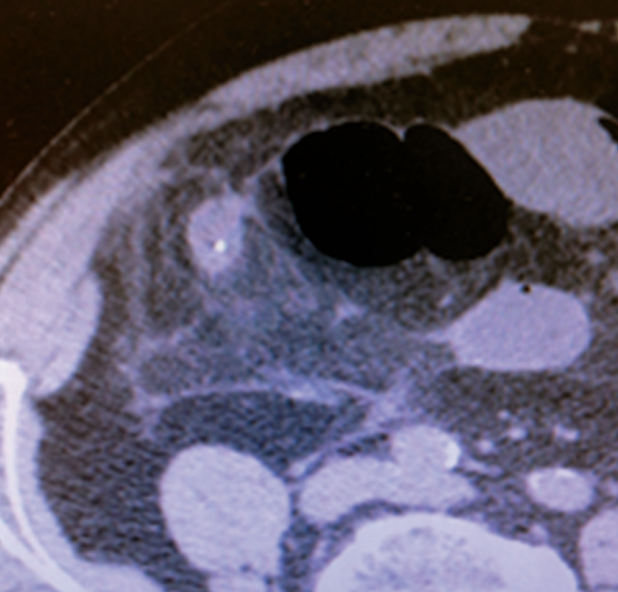

Complications of laparoscopic gastric banding: detection and treatment

Laparoscopic adjustable gastric banding (LAGB) is a popular and effective surgical option in the management of obesity and related metabolic diseases. Throught this study we analyzed the most common complications of this procedure.